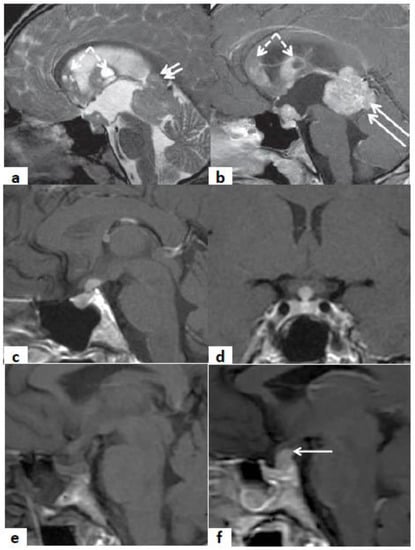

Figure 4.

Sagittal T2w (a) and CE-T1w (b) MR images. A case of a 20-year-old male patient affected by multifocal germinoma. The MR images show a pathologic tissue that involves the anterior portion of the third ventricle and the pineal gland (arrows). The multiple ependymal contrast-enhanced nodules (frecce tratteggiate) are suggestive of metastatic dissemination (dashed arrows). Sagittal (c) and coronal (d) MR CE-T1w images. A case of an 18-year-old female patient affected by Langerhans cell histiocytosis. The MR images show a contrast-enhanced pathologic tissue that involves III ventricle infundibulum. The pituitary gland shows a normal size. Sagittal MR T1w (e) and CE-T1w images (f). A case of a 50-year-old female with III ventricle infundibulum and pituitary stalk metastasis of breast cancer. The MR images show a pathologic contrast-enhanced tissue that involves III ventricle infundibulum and the pituitary stalk (arrow in (b)). The hyper-intense signal of the neuro-pituitary is lost on the T1-w image.